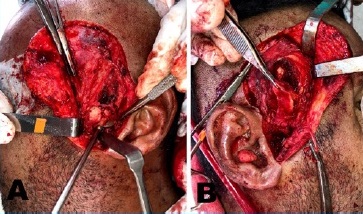

Based on clinical aspects, the clinician planned ankylotic block removal and interposition of a temporal flap. The procedure was performed in a surgical center under general anestesia and nasotracheal intubation. The Al-Kayat incision was employed to expose the TMJ region bilaterally for better exposure of the fused area and temporal musculature for rotation of the pedunculated flap (Figure 3).

Low condylectomy was performed bilaterally using a Lindemann bur. A chisel and hammer were used to disconnect the condyle from the glenoid cavity. Then, reanatomization of the joint surface was performed with a multi-laminated bur. After condylar arthroplasty, muscular interposition of the pedunculated flap of the temporal muscle was conducted, filling the joint cavity, using Vicryl 3.0 for its fixation and covering the TMJ region, thus reducing the chances of recurrence (Figure 4).